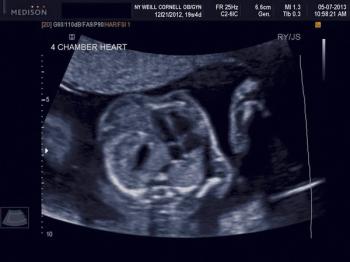

While several fetal anomalies can be diagnosed early in the pregnancy, second-trimester ultrasound can identify or exclude even more conditions. The second slideshow of our ultrasounds collection includes the second-trimester anomalies of the body and limbs that shouldn't be missed.

Ultrasound imaging is a key prenatal tool for revealing structural anomalies that may point to genetic conditions. This slideshow is Part 1 of our collection of ultrasound anomalies and includes first-trimester anomalies and second-trimester anomalies of the head and brain. Part 2 will discuss second-trimester anomalies of the body and limbs.